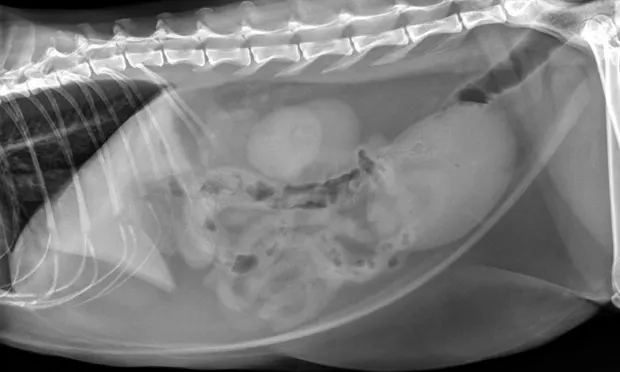

Figure 1. The urinary bladder appears large and there is bilateral renomegaly in this right lateral view; dystrophic mineralization is present in the right kidney.

At initial examination, Ivan was alert and responsive with heart rate, respiratory rate, and temperature within normal limits. He was estimated to be 5% dehydrated and had a large, firm, nonexpressible bladder. He was sedated with 0.015 mg/kg IV of buprenorphine, 0.2 mg/kg IV of midazolam, and administered a total of 2.5 mL of propofol IV for urinary catheter placement. A 5-French red rubber catheter was placed with slight resistance and maintained in place with butterfly tape and stay sutures. A CBC, serum chemistry panel, and plain abdominal radiographs (Figure 1) were performed.